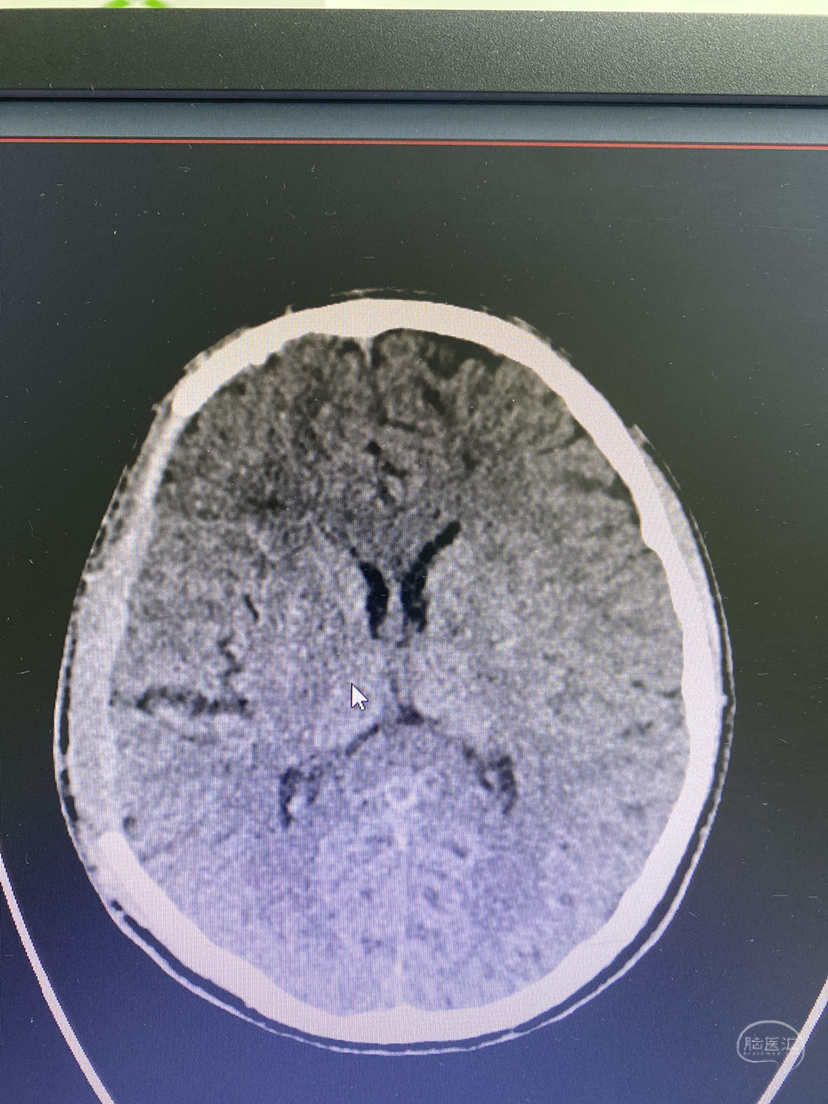

术后2月,修补前头颅CT